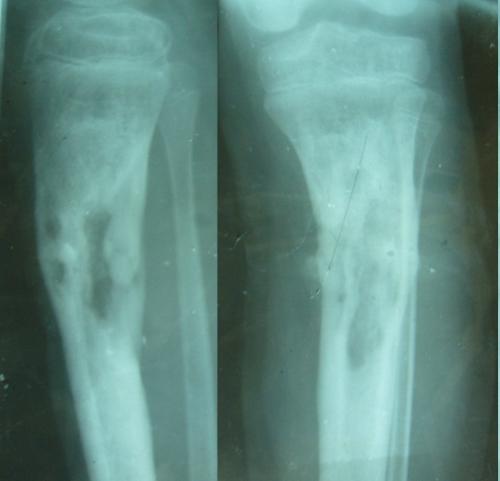

这一点,在著名的Cierny-Mader骨髓炎分型中表现的最为明显。1985年,Cierny和Mader两位医生为了更好的描述不同类型骨髓炎治疗方法,提出了著名的Cierny-Mader分型[3]。下图的“II型”骨髓炎,就是最典型浅表型骨髓炎。这种就是感染只累及到骨头的表面,没有影响骨髓腔,但是它也是骨髓炎。